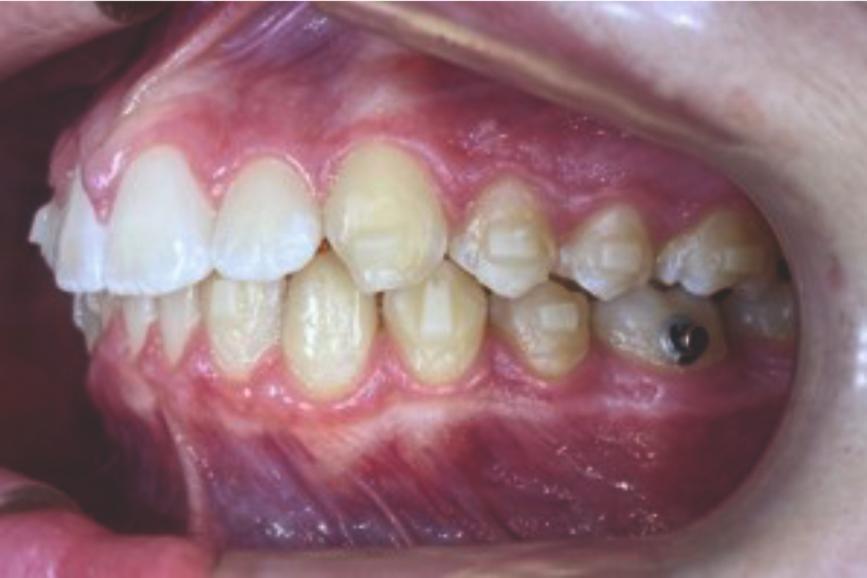

Chief complaint: We present the case of a 12-year-old female patient who came for an orthodontic evaluation, motivated by a family history of treatment. Clinical and radiographic analysis revealed a skeletal Class II malocclusion with molar and canine relationships also in Class II, moderate crowding in both arches, a deviation of the dental midline, and ectopic eruption of tooth 13. No functional issues with breathing or swallowing were observed, and oral health was generally good. A slight mandibular retrusion was noted in the soft tissue profile. A treatment plan was proposed using the Angel Aligner Pro system, aiming to correct dental misalignments and improve facial harmony through a minimally invasive, growth-adapted approach.

Clinical examination and diagnosis

- Woman ; 12/3 years

- Skeletal Class II

- Molar and canine Class II

- Upper and lower dentoalveolar compression

- Increased overjet and overbite

- Upper midline deviated 0,5 mm to the right

- Moderate upper and lower crowding